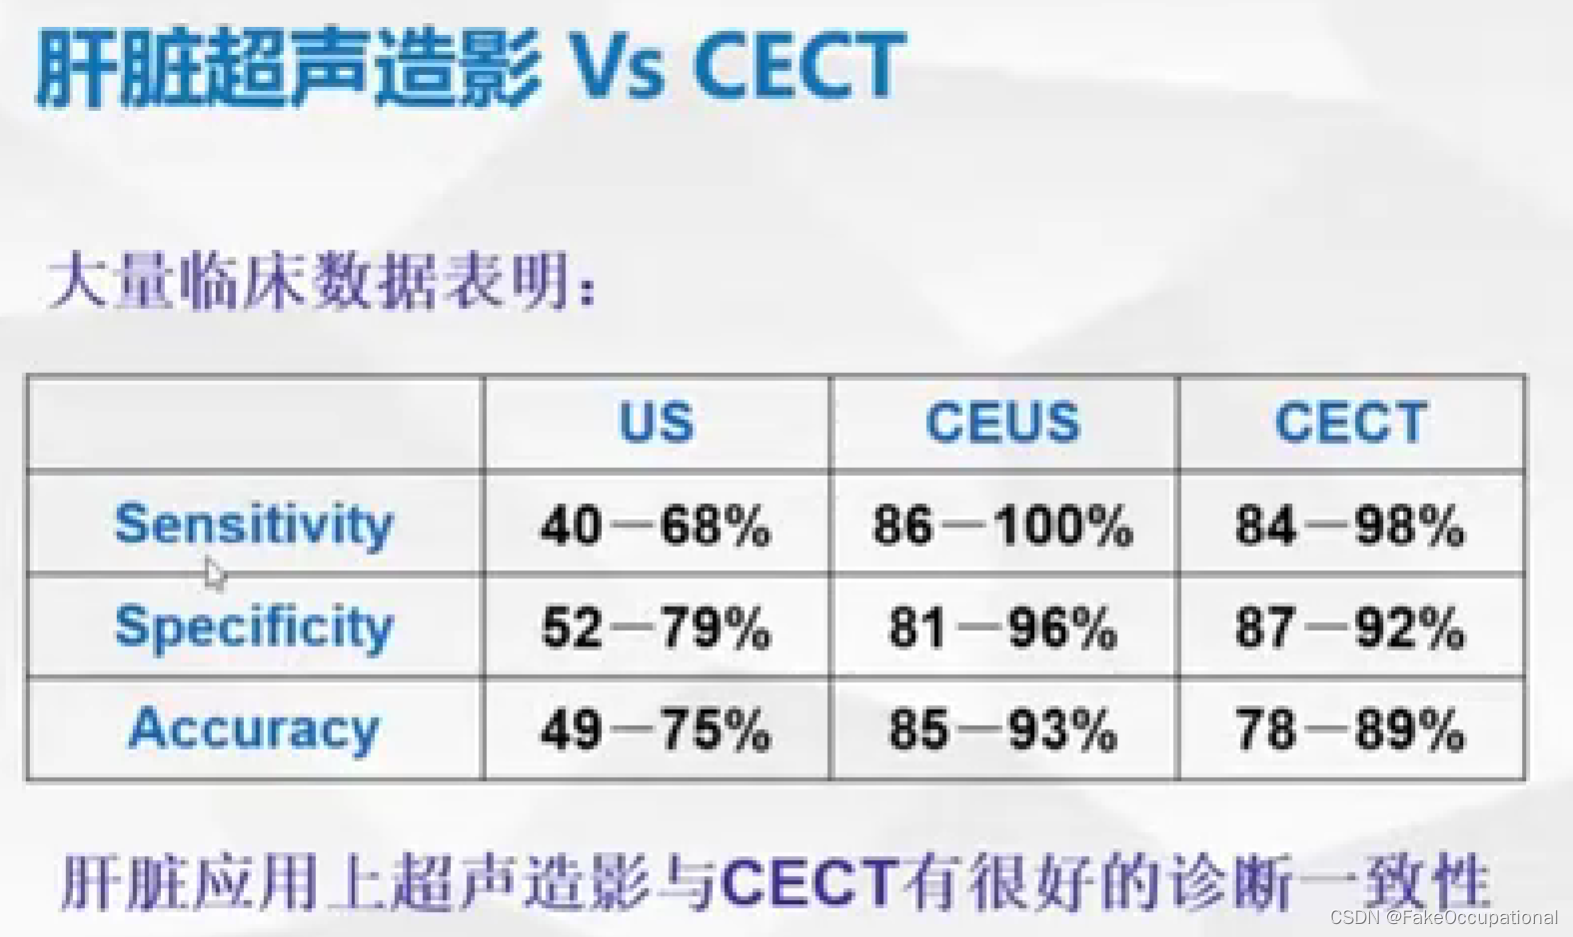

2.超声造影

- 超声更多起一个筛查的作用,定性需要造影或者其他设备的辅助